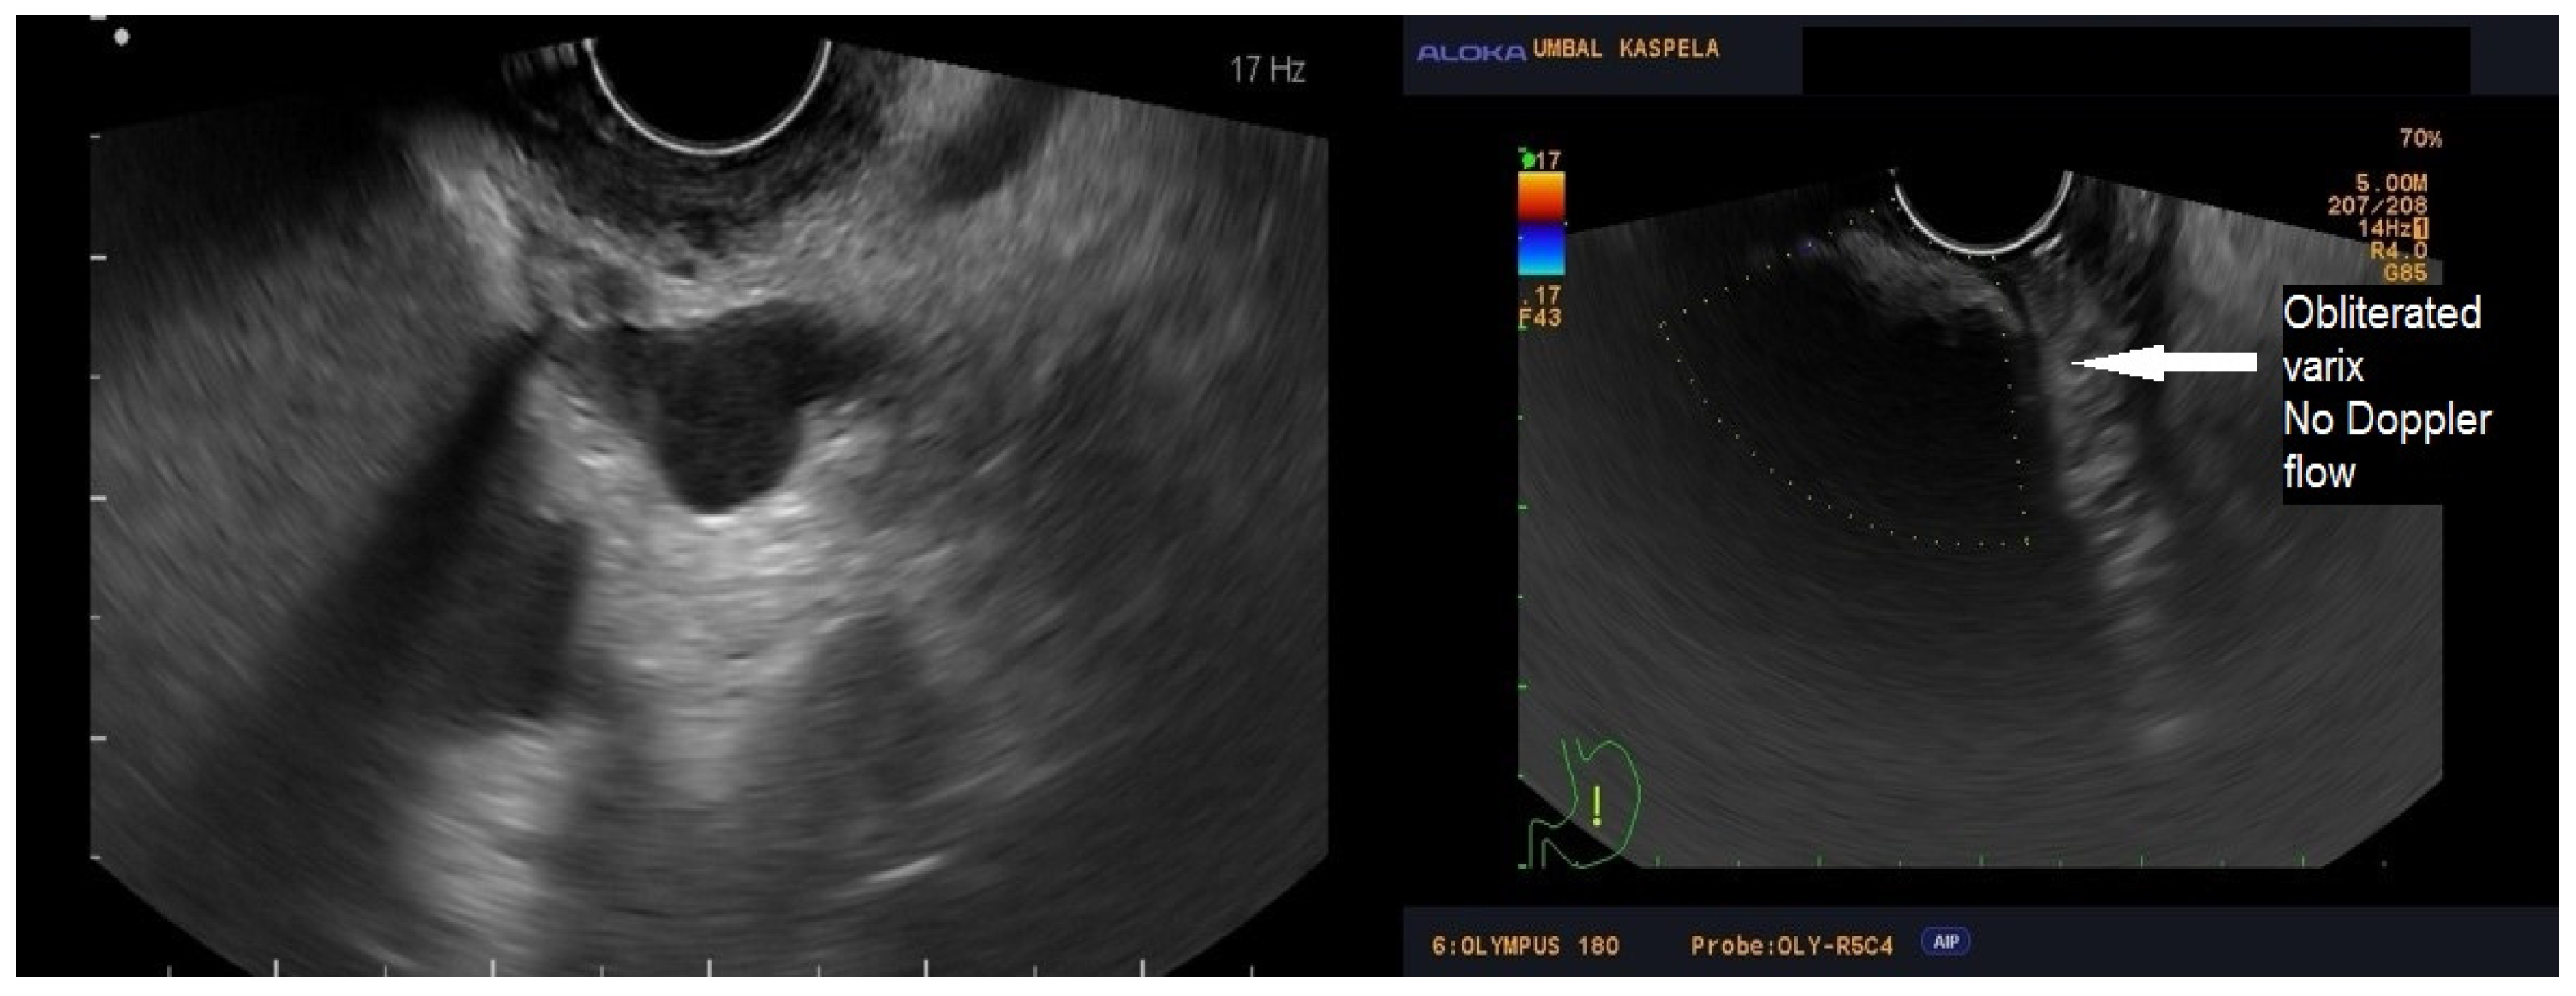

2.2. Technique Description

2.3. Post-Procedure